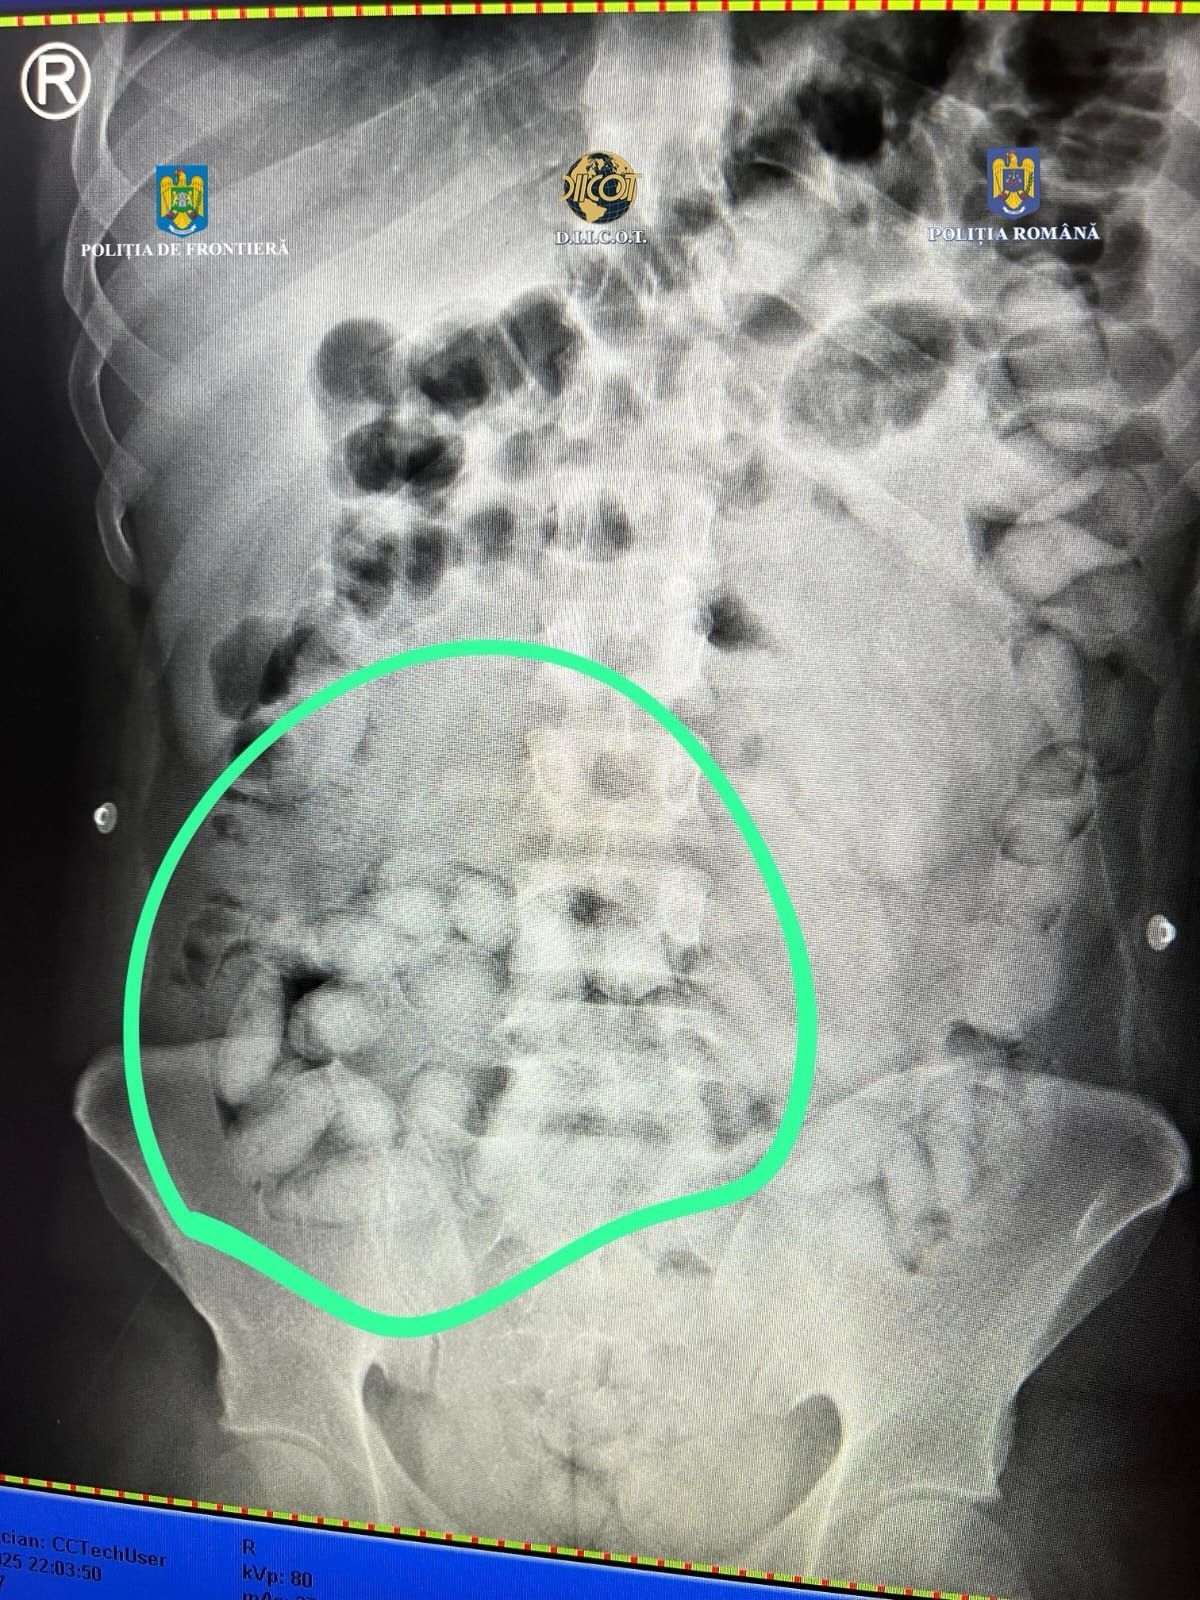

În urma controlului efectuat cu ajutorul unui scaner cu raze X, în interiorul abdomenului inculpatului au fost observate mai multe formațiuni neobișnuite, care nu corespund anatomiei umane. În consecință, inculpatul a fost condus la o unitate spitalicească, unde, pe parcursul internării, a eliminat un număr de 62 de cașete, ce conțineau aproximativ 350 de grame de substanță pulverulentă (în prezent aflată în curs de expertizare)", a transmis, vineri, DIICOT într-un comunicat de presă.